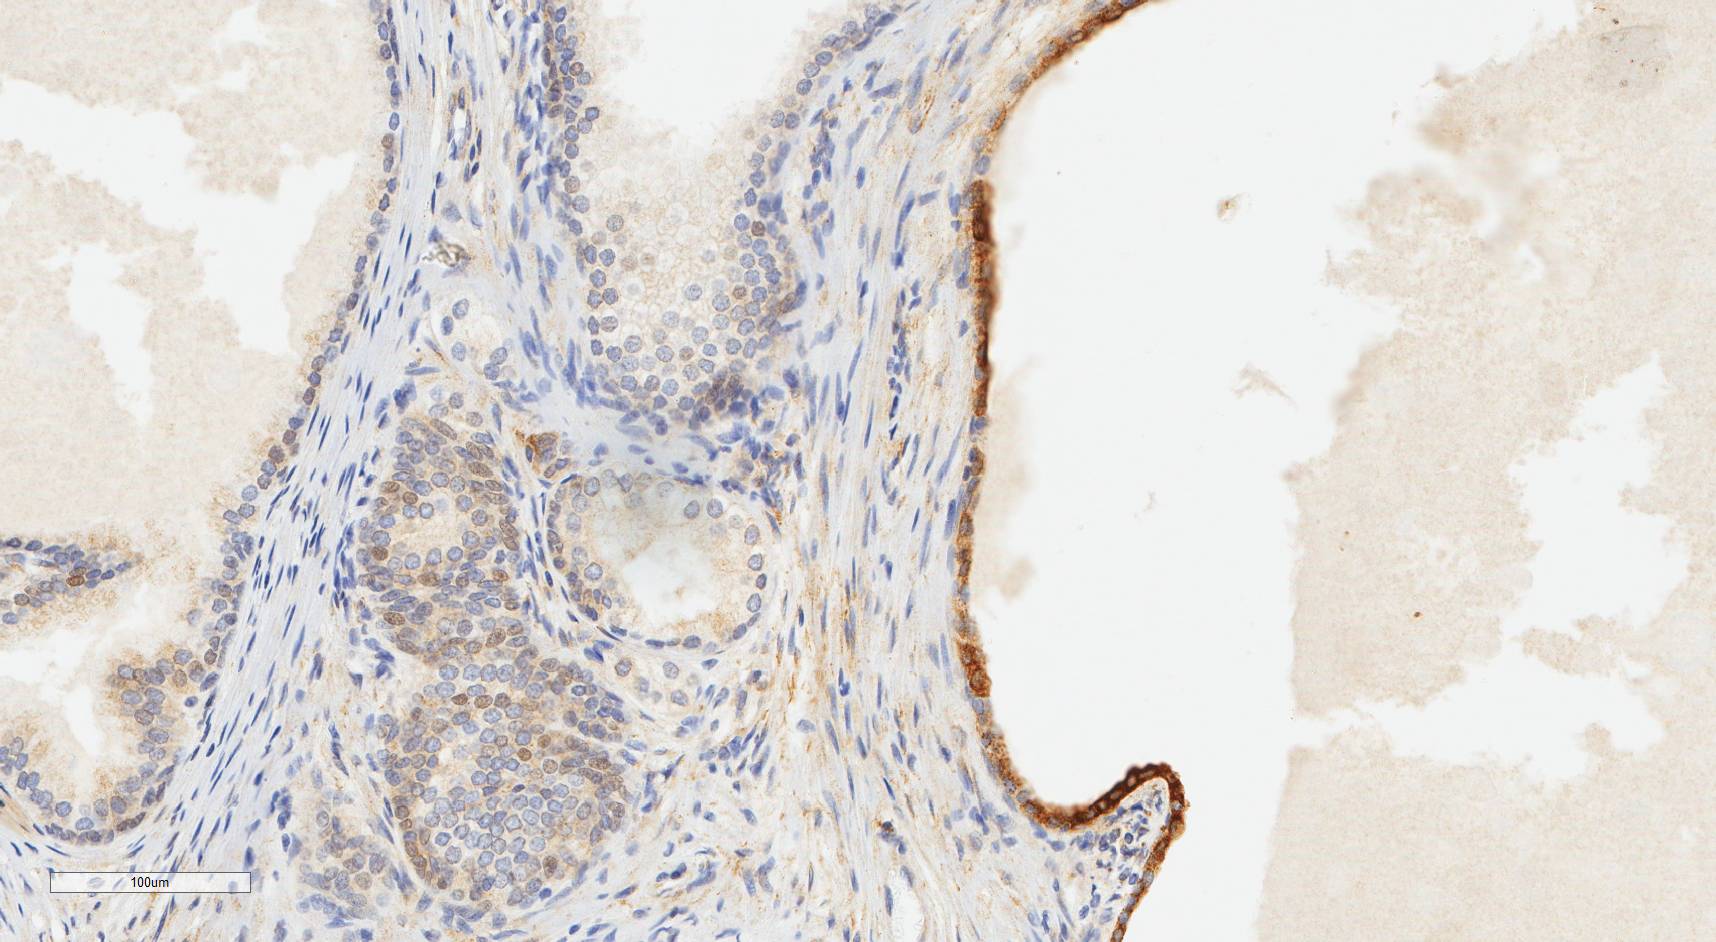

Laminin N terminus alpha31 (LaNt a31) is a really interesting laminin-related protein that the Hamill lab has been investigating for a while. Until recently, our studies focused entirely on the epithelial tissues of the skin, the surface of the eye and oral squamous cell carcinoma. However, we’ve always known that this relatively unstudied protein is also expressed by other tissues. As a first (and really important) step to understanding what this protein’s role is in tissue function, we used our new mouse monoclonal antibodies against the human form of LaNt a31 to screen a wide-range of human tissues.

Below you can see some of our favourite images from the selection. Click on an image to view as a slideshow.

You can see the whole story in the paper by Lee Troughton et al., available here.